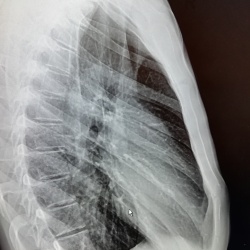

Мужчина 40 лет. Диагностическая  флюорография. Пришел на контроль, был поставлен диагноз 01.11.25 пневмония с\д, справа, в другой клинике. Смущает тень, которая видна только на задней проекции,...